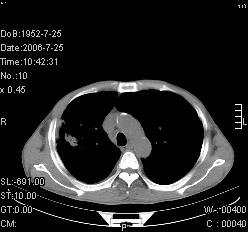

患者,男,54岁,咳嗦,咳痰20天。抗炎治疗2周。现esr76mm/h,目前患者症状明显好转,但发现两次ct片未见明显变化。两次分别做与7.25、7.31。第一次诊断右肺上叶炎症累计胸膜。大家看,从影像上内排除结核吗?

结核的可能性非常大,右上肺病变应该考虑干酪性肺炎。理由:

1.纵隔内多发淋巴结肿大。

3.虽经抗炎治疗肺窗病灶有所吸收、减小,但纵隔窗病灶形态、密度、范围无明显变化。如果是单纯的大叶性肺炎,“抗炎治疗2周,目前患者症状明显好转”病灶应该基本消散了,至少也处于吸收消散期,密度变淡、范围变小。同时本病例所示其内的密度不均匀,见多发大小不一空洞样影也不符合大叶性肺炎吸收消散期表现。

病灶特点:片状 索条 结节混杂影,部分融合,密度不均,广泛累及相应胸膜.

临床治疗;二周未吸收.但症状好转.

多考虑:肺结核.